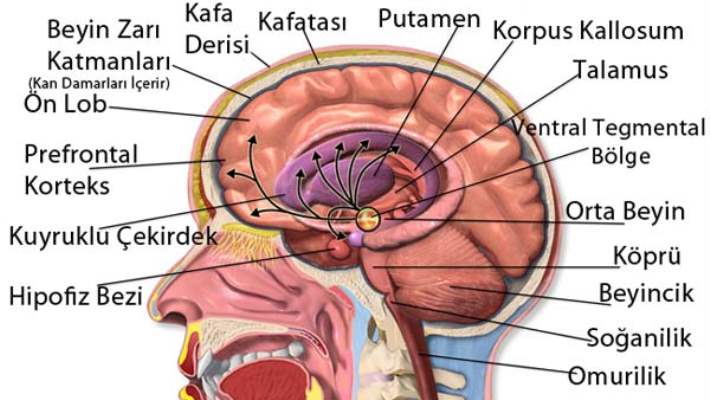

Beyin tümörü uyku hali. Yetişkinlerde ikincil beyin tümörleri birincil beyin tümörlerinden çok daha yaygındır. Ancak şikayetler çok daha çeşitlilik gösterebilir. 1925 yılından beri bilinen bu beyincik tümörü çok ayrı hücresel ve klinik özellikeri olan ve oldukça habis karekterli bir beyincik tümör tipidir beyinciğin çocuklarda en sık tümörü olup tüm primer beyin tümörlerininin 4 10 teşkil ederler. Patoloji alındı ondada tam teşhis konulmadı.

Uykuyu kontrol eden sinirler beyin sisteminde yer aldığı için sürekli uyku problemini çözmek için nöroloji bölümüne gitmeniz gereklidir. İkincil beyin tümörleri en sık kanser öyküsü olan kişilerde görülür. Denge kaybı uyku hali gözde görme sorunları duyma sorunları el ya da ayaklarda his sorunları ruhsal değişiklikler halüsinasyonlar görebilir yemek yeme sorunları yutkunma sorunları yemek yeme sorunları halsizlik trombosit düşüklüğü lökosit. Sadece uyku hali be yorgunluğu vardı.